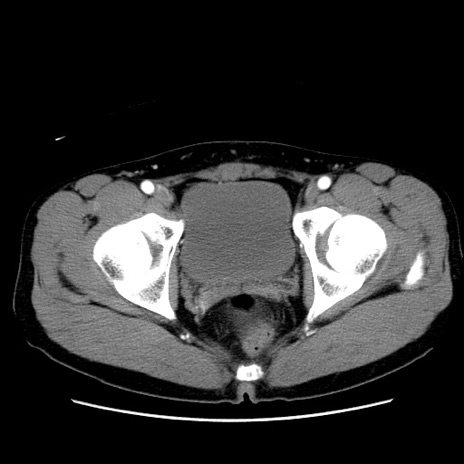

症例36(横断像)

【症例】20歳代 男性

【主訴】心窩部痛

【現病歴】今朝より上腹部痛あり。一旦軽快していたが再度出現したため救急要請。昨日夕に白身の魚を含む刺身を食べた。

【身体所見】BP 136/89mmHg、HR 74/min、BT 37.0℃、腹部:膨満、軟、心窩部に圧痛あり。反跳痛なし、筋性防御なし、腸雑音やや亢進あり。

【データ】WBC 17700、CRP 0.48